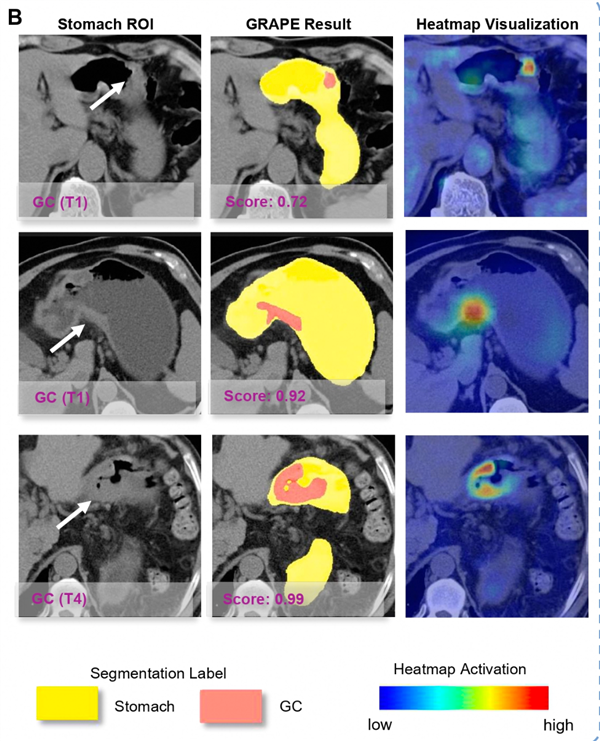

这一下,团队信心爆棚,开始在全国16个中心,上万份数据上进行验证。最终,这个名为GRAPE的AI模型,在超过7万人的真实世界数据里,交出了一份逆天答卷:它的胃癌检出率能达到17.7%以上!

那时的影像科医生,根本没往胃癌上想,报告也是正常的。可当胡灿把那张半年前的片子,放进了AI模型里,几秒钟后,屏幕上弹出了红色的警示,AI清晰地在胃部勾勒出了一个区域——早期胃癌。

真实案例测试中,患者在诊断前 6 个月拍的旧CT片,被 GRAPE 提示63.64%概率患有胃癌。